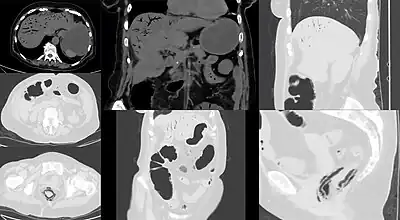

![]() | |

Computed tomography (CT) showing dilated loops of small bowel with thickened walls (black arrow), findings characteristic of ischemic bowel due to thrombosis of the superior mesenteric vein. | |